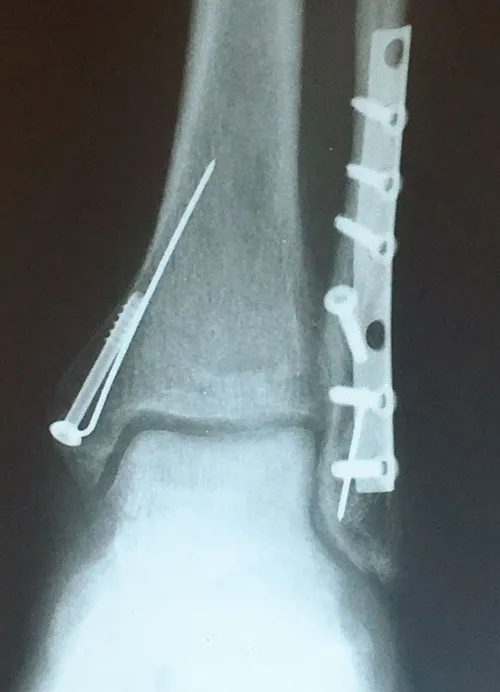

Preop and Postop ORIF Posterior Malleolus Fracture with associated Fibular fracture

Preop

Postop